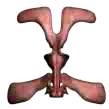

Bladder/Urethra

The bladder is a distensible organ located just above the pelvic floor. It is responsible for collecting urine prior to elimination. The urethra is a duct that connects to the bladder, allowing the bladder to drain.